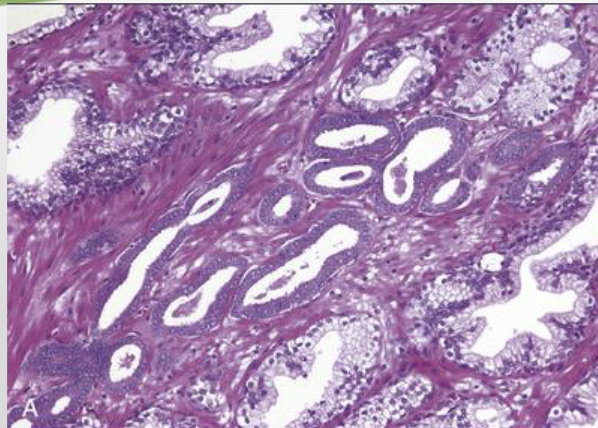

the following histopathology are signs of…?

• Hyperplastic acini

• Tightly packed, tall columnar epithelial cells with small basal nuclei

• Sometimes irregular papillary folds of epithelium

benign prostatic hyperplasia (BPH)